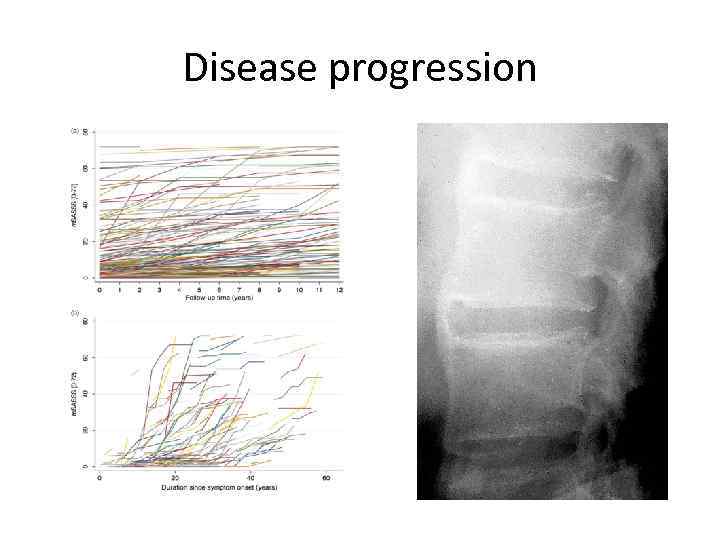

Disease progression